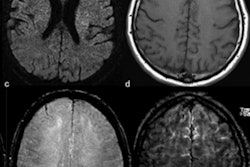

The study included 50 of 235 patients with COVID-19 admitted to the intensive care unit (ICU) between March 1 and April 18 who developed neurological symptoms. Of these 50 individuals, 27 underwent brain MRI scans (54%); 44% had acute findings. Ten of the 27 patients who had brain MRI showed cortical signal abnormality on fluid-attenuated inversion-recovery (FLAIR) protocols; three patients showed accompanying subcortical and deep white-matter signal abnormality on FLAIR images.

Contrast-enhanced cranial 1.5-tesla MRI examination of a 59-year-old intubated male patient with altered mental status despite tapering of sedoanalgesia. Axial FLAIR images at level of midbrain (a) and centrum semiovale (b) demonstrate prominent symmetric white matter hyperintensity and right frontal cortical hyperintensity. There is also prominent linear hyperintensity within frontal sulci. Axial b2000 DWI (c) shows frontal increased signal with corresponding low apparent diffusion coefficient (ADC) (images not provided). Axial T1-weighted imaging (T1WI) (d) shows right frontal sulcal effacement. Postcontrast T1WI (e) shows mild pial-subarachnoid enhancement. Axial susceptibility-weighted imaging (SWI) at the level of corona radiata (f) and centrum semiovale (g) demonstrates blooming artifact in the frontal sulci. Postcontrast FLAIR (h) depicts the bilateral leptomeningeal enhancement. Caption and images courtesy of the RSNA."Current evidence suggests an association of neurologic manifestations with COVID-19 infection including acute stroke and altered mental status," the group wrote. "Neurotropism of coronavirus may account for the relatively high percentage of neurologic involvement. In addition to neurotropism, another potential mechanism for neurologic manifestations might be related to cytokine storm syndrome."